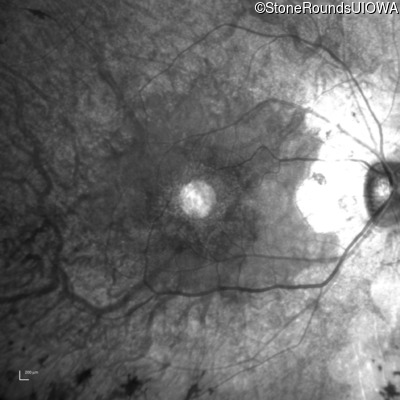

Infrared Fundus Photograph - Left - 20/25 sc

Exemplar